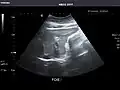

Abdominal Ultrasound (Full Exam)

STRUCTURED REPORT

(Technique: Transabdominal ultrasonography; Device: Toshiba Aplio XG)

Liver: Diffusely homogeneous and normal in echogenicity. No focal mass or contour nodularity. No intrahepatic biliary ductal dilatation.

Portal Vein: Patent main portal vein.

Gallbladder: No stones, wall thickening, or pericholecystic fluid.

Common Bile Duct: Nondilated measuring 1.3 mm at the level of the porta hepatis.

Pancreas: Visualized portions unremarkable.

Spleen: Normal in size.

Kidneys: Right and left kidneys measure 11.5 cm and 12 cm in length respectively. No hydronephrosis. Small left lower pole kidney cyst.

Ascites: None.

Aorta: Visualized portions normal in caliber, 16 x 15 mm.

IVC: Normal.

IMPRESSION:

Normal abdominal ultrasound.